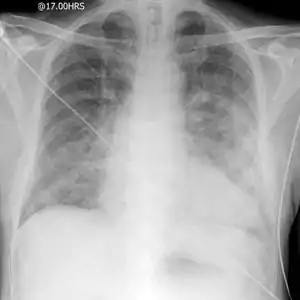

![]() Класична рентгенограма набряку легень Класична рентгенограма набряку легень | |